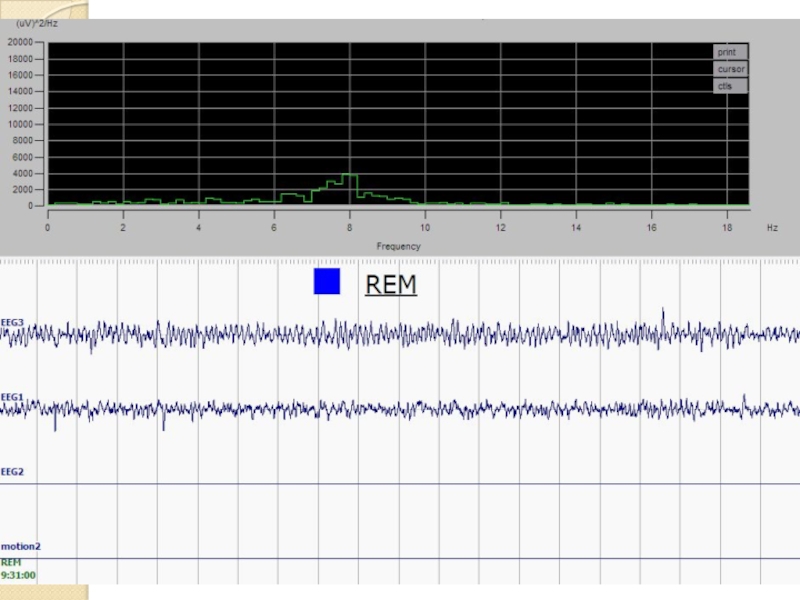

- 12. Стадирование сна по ЭЭГ Примеры записей ЭЭГ и движения Бодрствование Медленный сон Быстрый сон

- 13. Пример ЭЭГ бодрствования